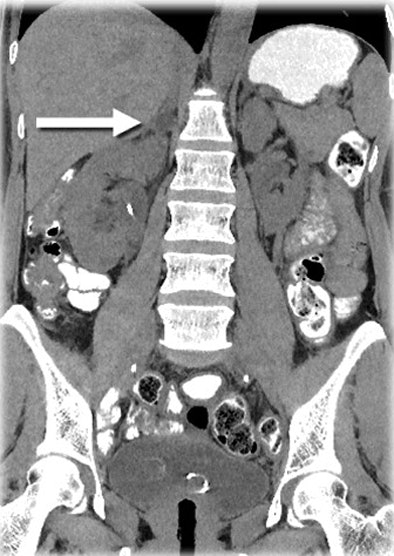

| Unlike filtered back projection reconstruction (above), which relies on assumptions about the x-ray beam, MBIR (below) analyzes the beam at three points: at the focal spot, as it passes through the patient's body, and, finally, at the level of the x-ray detector. |